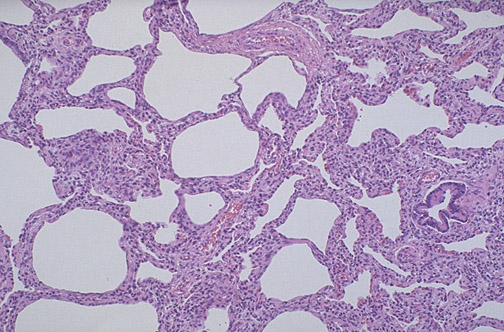

![]() | A later complication of prematurity should the baby survive the immediate neonatal period, during which time mechanical ventilation was necessary, is bronchopulmonary dysplasia (BPD). With BPD, there is interstitial fibrosis and inadequate alveolar development for good pulmonary function. Respiratory distress can continue for months to years. |